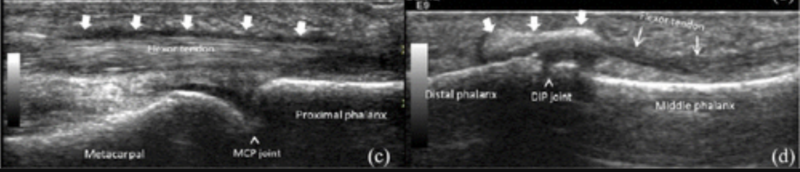

関節超音波

RA同様、関節液貯留・滑膜肥厚・骨びらん等の描出が可能

その他、腱鞘炎・腱滑膜肥厚・軟部組織石灰化・皮膚肥厚の検出も可能

関節滑膜炎±浸出液・腱鞘炎がSSc関節炎の所見として最多(Eur J Radiol 2011; 77(2): 254–257.)

MCP関節の滑膜肥厚

硬化性腱鞘炎・石灰化はSSc関節炎で特異的とされる(Arthritis Care Res 2012; 64(8):1244–1249.)

DIP関節屈筋腱症に沿った石灰沈着(⇩)、局所的な石灰化(↓)

滑膜炎・骨びらんの検出感度が高い

CMC関節の関節内石灰化(^)、遠位伸筋腱内の石灰化(*)、皮膚びまん性肥厚・局所的な破壊(⇐)